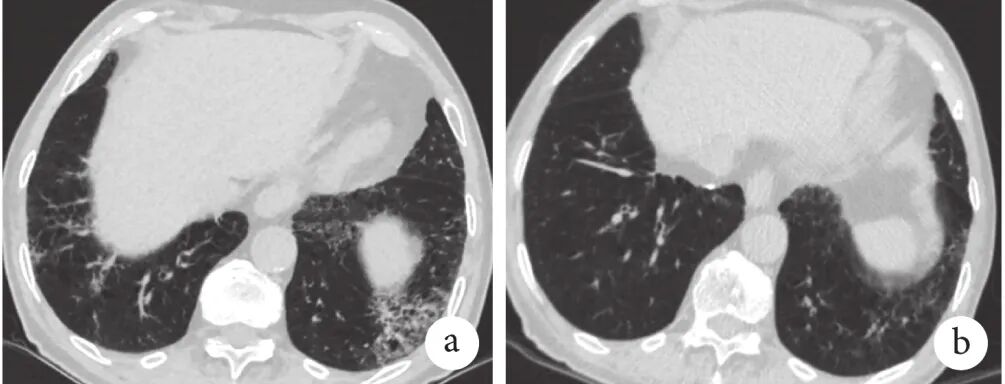

患者2,男,89岁,吸烟20包年,咳嗽、咳白色黏痰、活动后喘憋10年,诊断“慢阻肺”,规律使用ICS+LABA。7年前查出外周血嗜酸性粒细胞百分比升高(13.6%),5年前胸部HRCT示双肺散在磨玻璃影,2年前因发热入院,查外周血嗜酸性粒细胞百分比14.1%,血清IgE 7016 IU/mL,烟曲霉特异性IgE 14.8 kUA/L,烟曲霉特异性IgG(+),胸部HRCT示双肺多发斑片影,双肺肺气肿,双侧胸腔积液(图1),诊断ABPA,给予伊曲康唑200 mg、2次/d治疗,2个月后血清IgE降至2163 IU/mL,1年后复查胸部HRCT示双肺斑片影及胸腔积液吸收,患者持续用药,无急性加重。

图1 患者2的HRCT检查像

a. 2019年4月13日,显示双肺多发斑片影,双肺肺气肿,双侧胸腔积液;b. 2019年11月19日,治疗后肺部斑片影及双侧胸腔积液吸收。